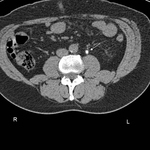

CT scan showing left renal stone (white arrow) with perinephric stranding around the left kidney (blue chevrons) and pyelonephritis

From the personal collection of Dr Kasra Saeb-Parsy